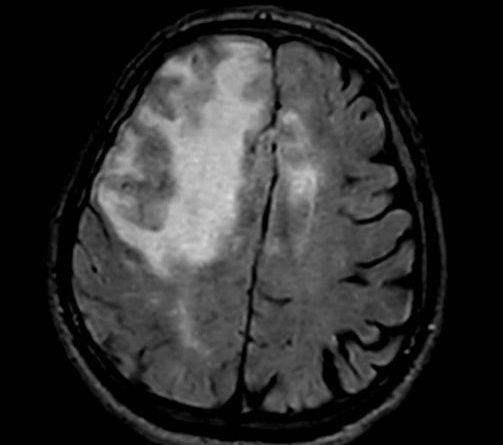

- A) Aksiyel planda FLAIR sekansta asimetrik kortiko-subkortikal vazojenik ödemi düşündüren yüksek sinyalli hafif ekspansil lezyonlar (turuncu ok).

- B) ADC haritasında kolaylaşmış difüzyon (mavi ok).